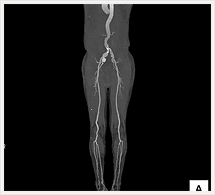

CTでは輪切り像の他にも立体的な画像(3D画像)を作成することもできます。そのためにはより細かくキレイな画像を撮影しなければなりません。当院では64列CTを導入しており、キレイな画像をより細かく撮影することができます。その画像を元に3D画像を作成することによって、より正確な手術のシミュレーションが可能になります。実際に手術をしたときの様子が、手術をする前に画像として見らます。外科系の手術には欠かせない技術となっておりますが、内科系でも血管内手術にも多く利用されております。

当診療放射線技術科では毎日各診療科に対して、その手術に最適な3D画像を提供しております。

以下にその3D画像を一部分紹介します。

下肢動脈